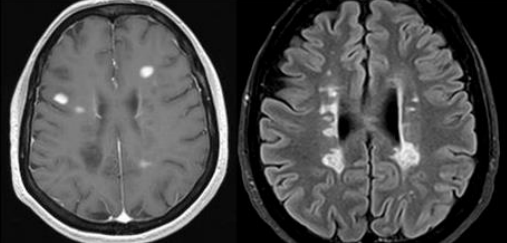

El pròxim dia 10 de Febrer de 2017 tindrà lloc en l’Hospital Universitari i Politènic la Fe de València (Aula H009) una reunió de Neurologia i Radiologia sobre Consens radiològic en diagnòstic i seguiment de l’Esclerosi Múltiple, organitzada pels Drs. Ventura Casanova i Luis Martí Bonmatí.